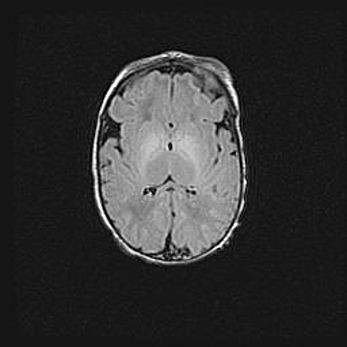

Церебральная ишемия II.

Возраст: 5 дней

Вес: 3400 г

Пол: женский

Окружность головы: 35 см

Срок гестации: 39 недель

Церебральная ишемия – это заболевание, характеризующееся недостаточностью (гипоксией) либо полным прекращением (аноксией) снабжения мозга кислородом по причине закупорки одного или нескольких сосудов. Это приводит к  что метаболическим расстройствам различной степени тяжести в тканях головного мозга, развитию коагуляционных некрозов и гибели нейронов.